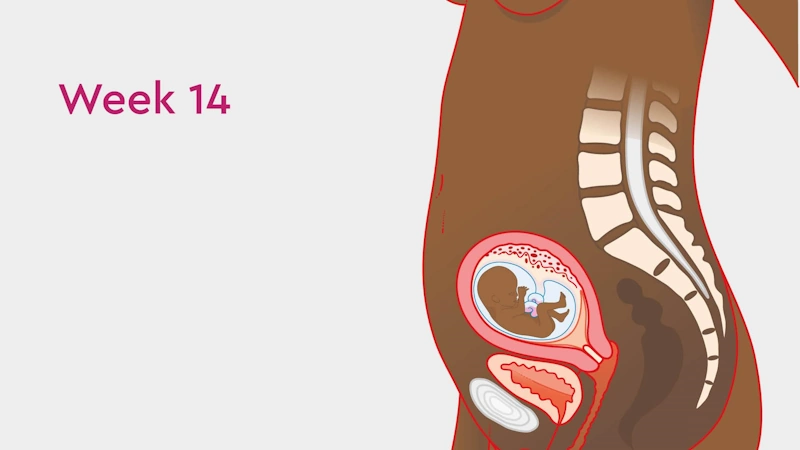

🔹 Uterine Growth and Belly Expansion

Your uterus is now about the size of a grapefruit, positioned roughly an inch (2.5 cm) below your navel. You may notice your belly becoming slightly more prominent — the first visible sign of pregnancy for many mothers.

When lying on your back, you may be able to feel the top of your uterus by gently pressing just below your belly button. Don’t worry — touching your abdomen won’t harm your baby. The amniotic sac and the strong uterine wall provide excellent protection.

At each prenatal visit, your obstetrician will measure the fundal height (from the pubic bone to the top of the uterus) to ensure that the baby’s growth matches the expected timeline.

💡 By week 16, your uterus should reach halfway between the pubic bone and the navel — a reassuring sign of normal development.